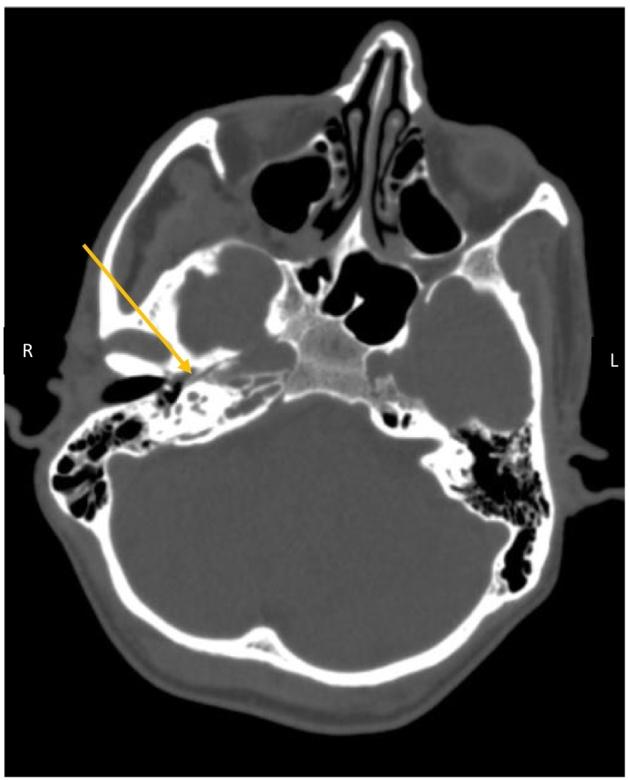

Gradenigo's syndrome (GS) is a triad (otorrhea, abducens nerve palsy, and pain in the trigeminal nerve distribution) of clinical findings that are caused by contiguous spread of petrous apicitis to the nearby neurovascular structures. Petrous apicitis is usually secondary to otitis media but atypical etiologies and absence of the classical triad pose a diagnostic challenge for physicians. We report a rare case of GS in an afebrile 55-year-old male who presented with unilateral headache, dysphagia and hoarseness (IX and X cranial nerve involvement), and diplopia with lateral gaze palsy (VI nerve involvement) in the absence of trigeminal neuralgia or a history of otitis media. Magnetic Resonance Imaging (MRI) revealed hyperintense lesions in the right petrous apex indicating petrous apicitis, the hallmark of GS. Prompt initiation of broad-spectrum antibiotics led to a marked improvement in dysphagia and voice quality on the 4th post-admission day, and complete resolution of symptoms by the end of the fourth week. This shows that GS can present even in the absence of clinically apparent ear infection and cranial nerve palsies may not be limited to the V and VI nerve in all cases. Physicians should be aware of such atypical manifestations as prompt radiological assessment followed by early antibiotics can prevent life-threatening complications from developing.

Gradenigo综合征(GS)是一种由岩尖炎向附近神经血管结构连续蔓延所致的临床三联征(耳漏、展神经麻痹及三叉神经分布区疼痛)。岩尖炎通常继发于中耳炎,但非典型病因及缺乏典型三联征给医生的诊断带来挑战。我们报告一例罕见的GS病例,患者为55岁男性,无发热,表现为单侧头痛、吞咽困难和声音嘶哑(累及IX和X颅神经),以及外展凝视麻痹伴复视(累及VI神经),无三叉神经痛或中耳炎病史。磁共振成像(MRI)显示右侧岩尖有高信号病变,提示岩尖炎,这是GS的标志。入院后第4天迅速开始使用广谱抗生素,吞咽困难和声音质量明显改善,到第四周结束时症状完全缓解。这表明即使没有明显的临床耳部感染,GS也可能出现,而且在所有病例中颅神经麻痹可能并不局限于V和VI神经。医生应意识到这种非典型表现,因为及时的影像学评估并尽早使用抗生素可预防危及生命的并发症发生。